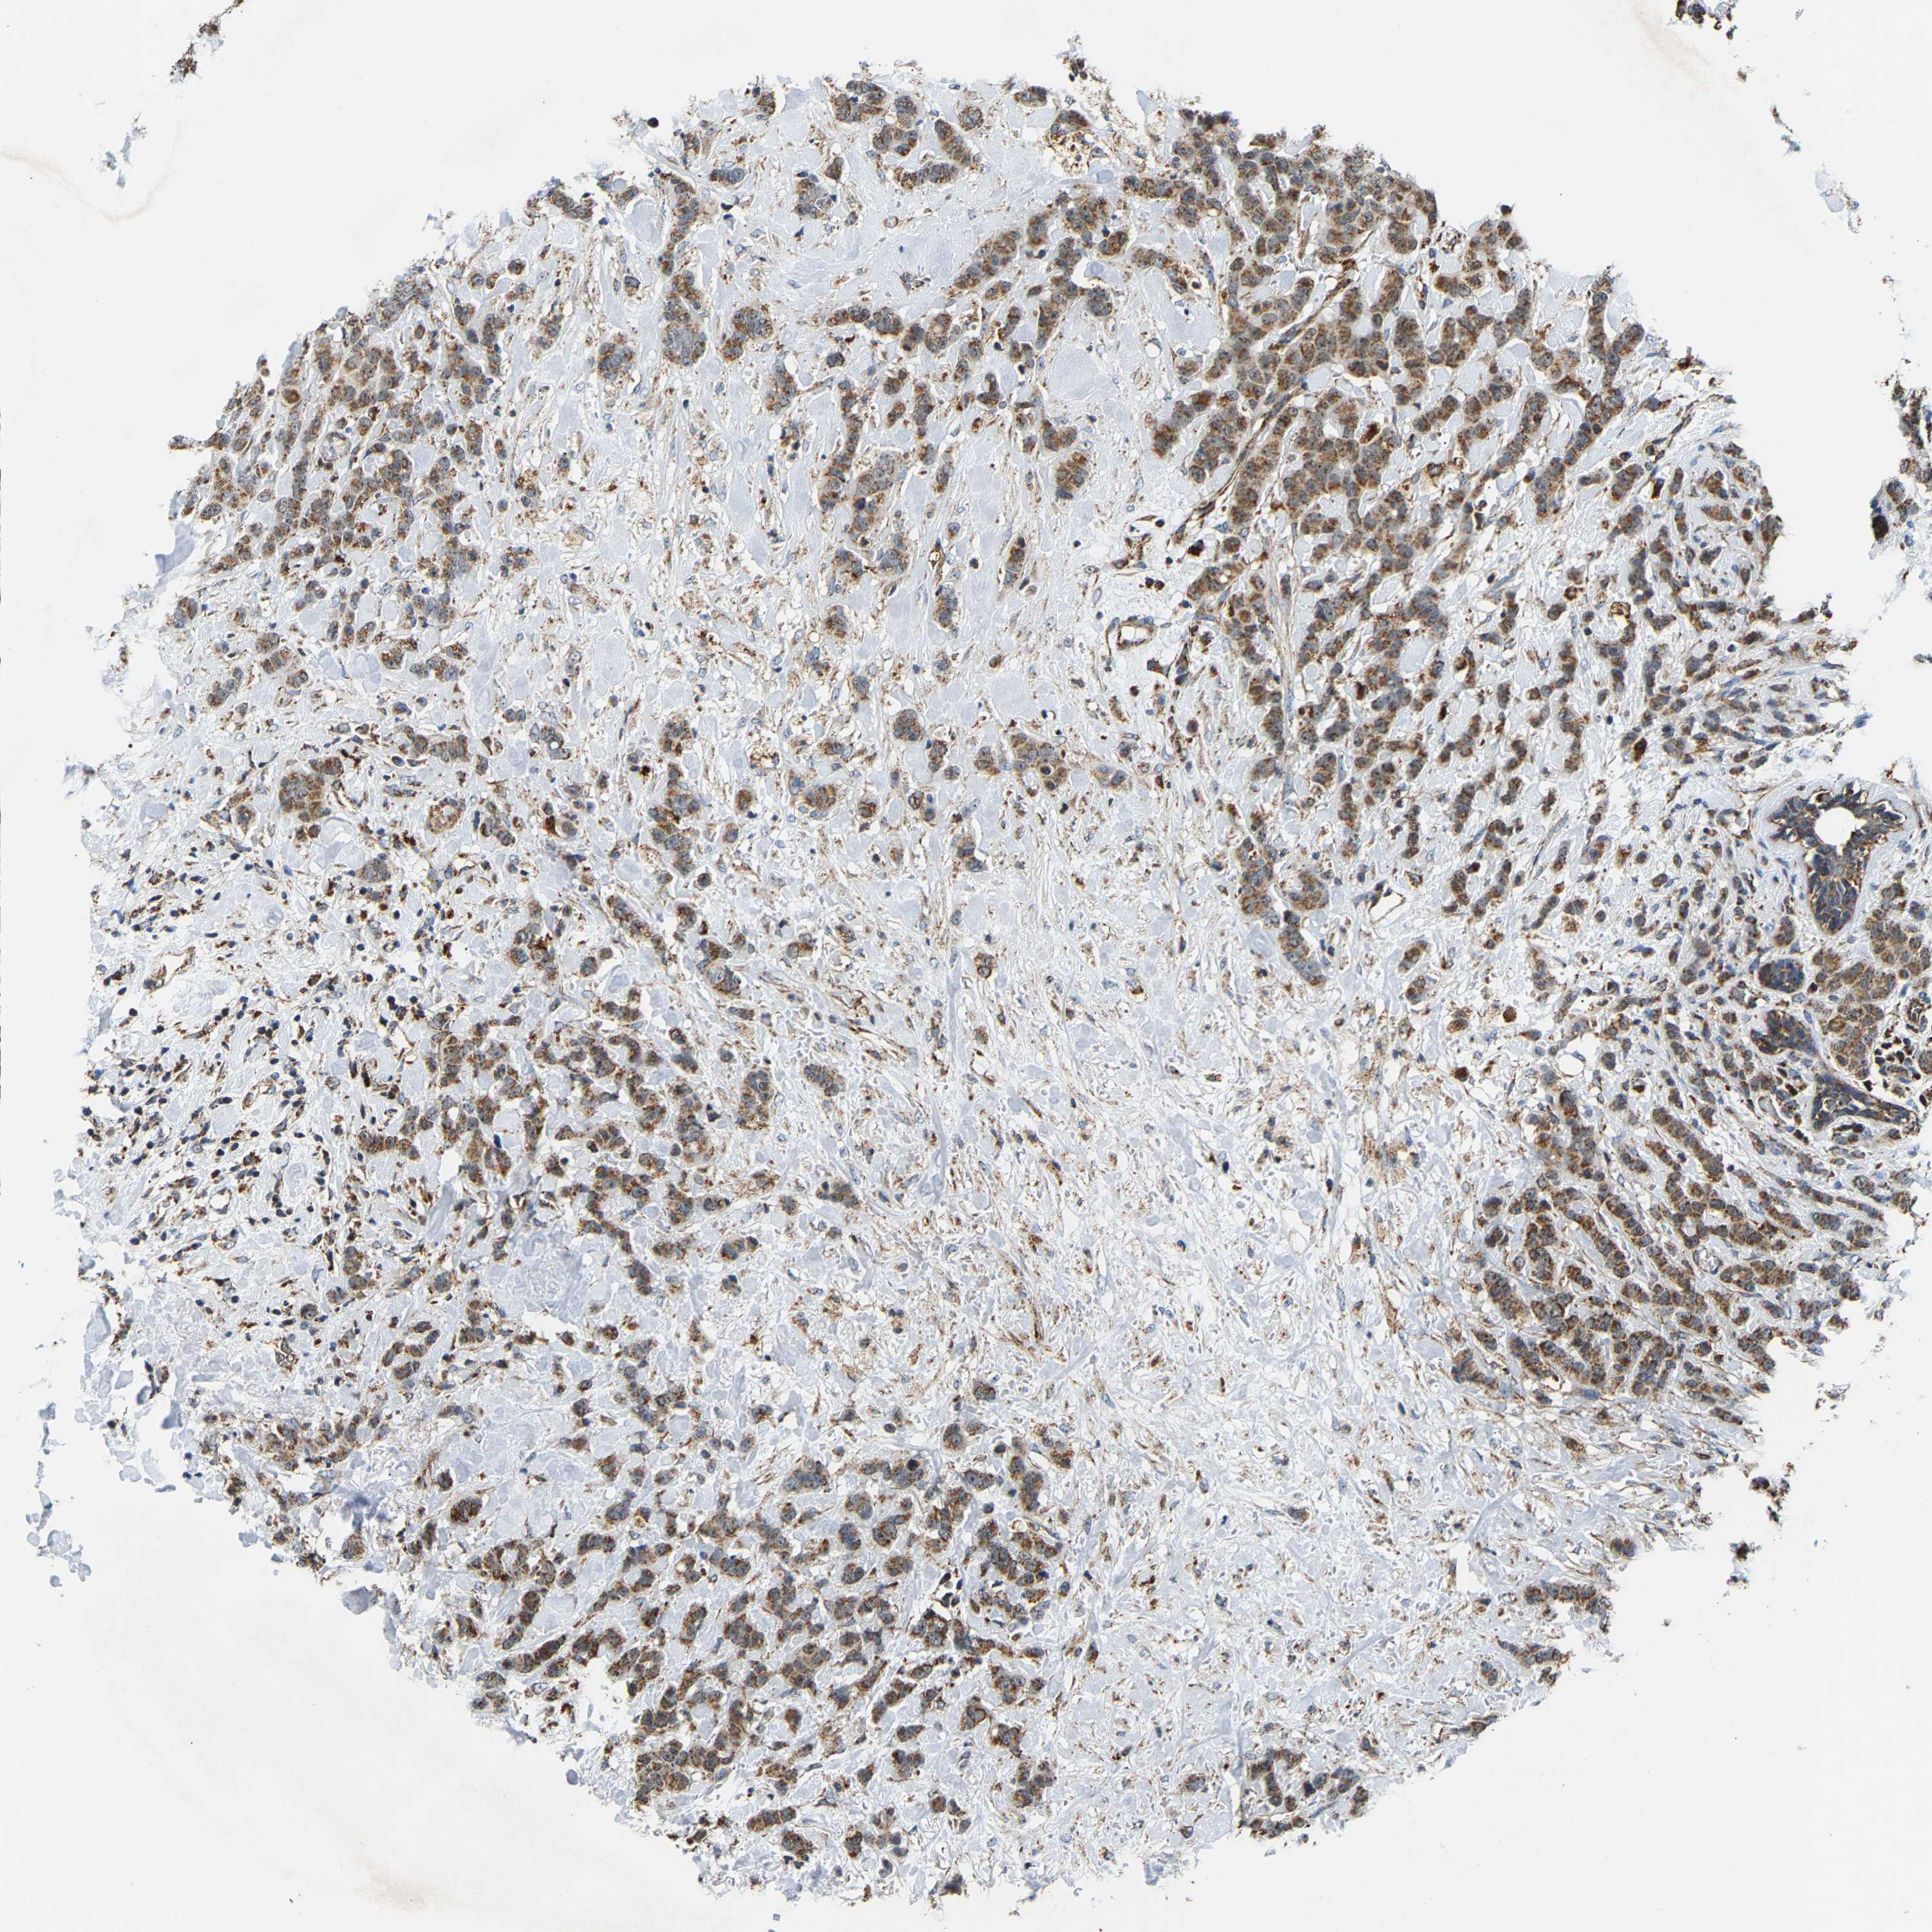

CANCER BREAST CANCER Show tissue menu

BRCA TCGA BRCA VALIDATION PROTEIN EXPRESSION